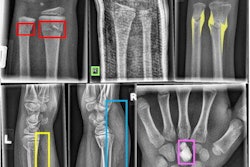

As a result, the researchers sought to explore the feasibility of an object-detection CNN, a type of deep-learning model that can detect objects and draw bounding boxes around them on images. The researchers first extracted 7,356 wrist radiographic studies -- 7,295 frontal images and 7,319 lateral images -- from their hospital's PACS.

One of three radiologists then reviewed and annotated each of the images -- including drawing bounding boxes of fractures. These studies were then used to train a deep-learning model based on the Inception-ResNet version 2 Faster R-CNN architecture. Of the 7,356 studies, 90% were used for training the CNN and 10% were used for validation.

Next, the researchers tested the model on 524 consecutive emergency department wrist radiographic studies and compared its findings with a reference standard of two radiologists reading in consensus. The model detected and correctly localized 310 (91.2%) of the 340 fractures seen on the frontal views and 236 (96.3%) of the 245 fractures found on the lateral views.